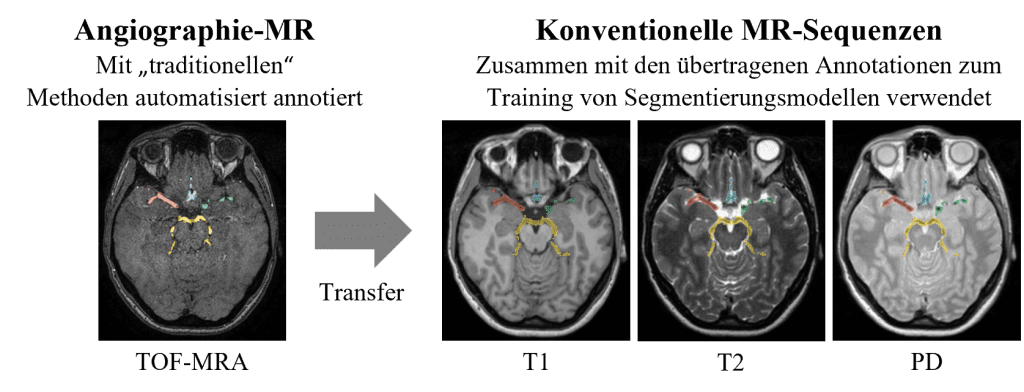

Die Forschenden der Abteilung Medizin-Informatik haben eine vollständig automatisierte Methode entwickelt, die die Gehirnarterien entlang des Circle of Willis segmentiert und vier Gefäßregionen (Anterior, Posterior, Links und Rechts) annotiert. Ihre Methode unterstützt drei verschiedene nicht-angiographische MR-Sequenzen sowie die angiographische TOF-MRA Sequenz. Hierfür wurde eine künstliche Intelligenz auf 555 Patient*innen des öffentlichen IXI-Datensatzes trainiert [3]. Für jeden Patient*in sind im besagten Datensatz die MR-Sequenzen PD, T1, T2 und TOF-MRA verfügbar. Die Segmentierungsaufgabe bei den angiographischen TOF-MRA Bilddaten konnte mit traditionellen Bildverarbeitungsmethoden automatisiert gelöst werden (siehe Abbildung 3), und die Annotationen wurden anschließend erfolgreich auf die nicht-angiographischen Sequenzen übertragen (siehe Abbildung 4). Die künstliche Intelligenz wurde daraufhin trainiert, die Segmentierungsaufgabe für alle vorhandenen Sequenzen zu meistern. Spezifisch wurden semantische Segmentierungsmodelle basierend auf künstlichen neuronalen Netzwerken (ANN) unter Verwendung des Frameworks nnU-Net entwickelt [4].

Abbildung 3: Die automatische Methode zur Annotation der Blutgefäße und Gefäßregionen in der angiographischen TOF-MRA Sequenz basiert auf traditionellen Bildverarbeitungsmethoden.

Abbildung 4: Die annotierten Blutgefäße aus der TOF-MRA Sequenz wurden auf die nicht-angiographischen Sequenzen (PD, T1, T2) übertragen. Der resultierende Datensatz aus Bilddaten und „Ground-Truth“ Annotationen wurde anschließend für das Training der Segmentierungsmodelle verwendet.